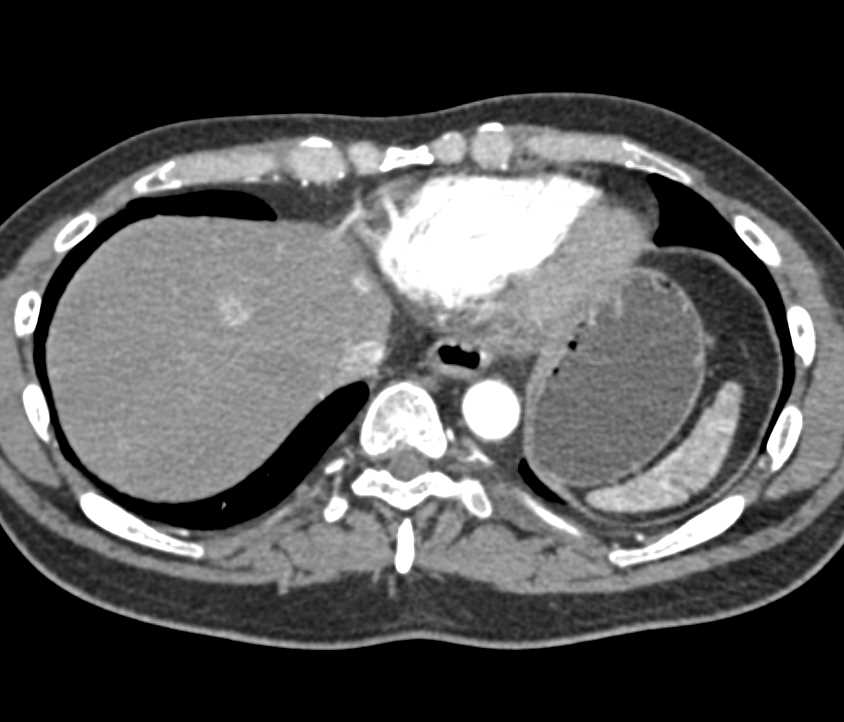

Hyopodense Liver Metastases Best Seen on Venous Phase Images